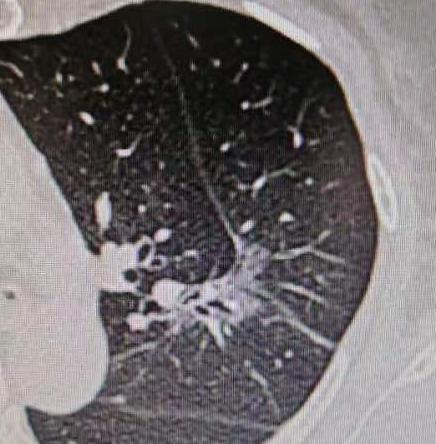

给大家分享一个特别的病例,这位65岁的女性患者,最近两个月,全身关节总是酸痛,而且越来越严重。幸好她有位亲戚是医生,就建议她做个全面体检。 这一查,果然发现了问题——肺里长了一个肿瘤,同时还请了风湿免疫科的医生会诊,也判断她有风湿方面的问题。 又做了进一步检查考虑是肺癌,幸运的是,全身检查下来没有发现转移。我们很快为她安排了手术,术后病理也证实了是“浸润性腺癌”。 手术过程倒是挺顺利,不过这位患者的肺部结构确实和一般人不太一样——她的左上肺叶自然分成了两叶,也就是固有段和舌段分开的。这种情况真的很少见,可能一百个人里也难找到一个。 另外,她的肺动脉有五支分支,走形也不典型,舌段的动脉是从气管前方走的。好在手术顺利完成,没有受到这些变异的影响。 最让人意外的是术后第二天,我们查房时问她关节还痛不痛,她说:“奇怪,好像不痛了。” 这其实就印证了这是“副癌综合征”的表现——肿瘤分泌的特殊物质进入血液循环,引起关节酸痛等症状。随着肿瘤被切除,症状也就自然缓解了。 这个病例提醒我们,当身体出现不明原因的关节疼痛时,除了考虑风湿免疫类疾病,也要警惕可能是肿瘤发出的信号。 特别是当常规治疗效果不好时,一定要做全面检查,找出真正的病因。[作揖][玫瑰]